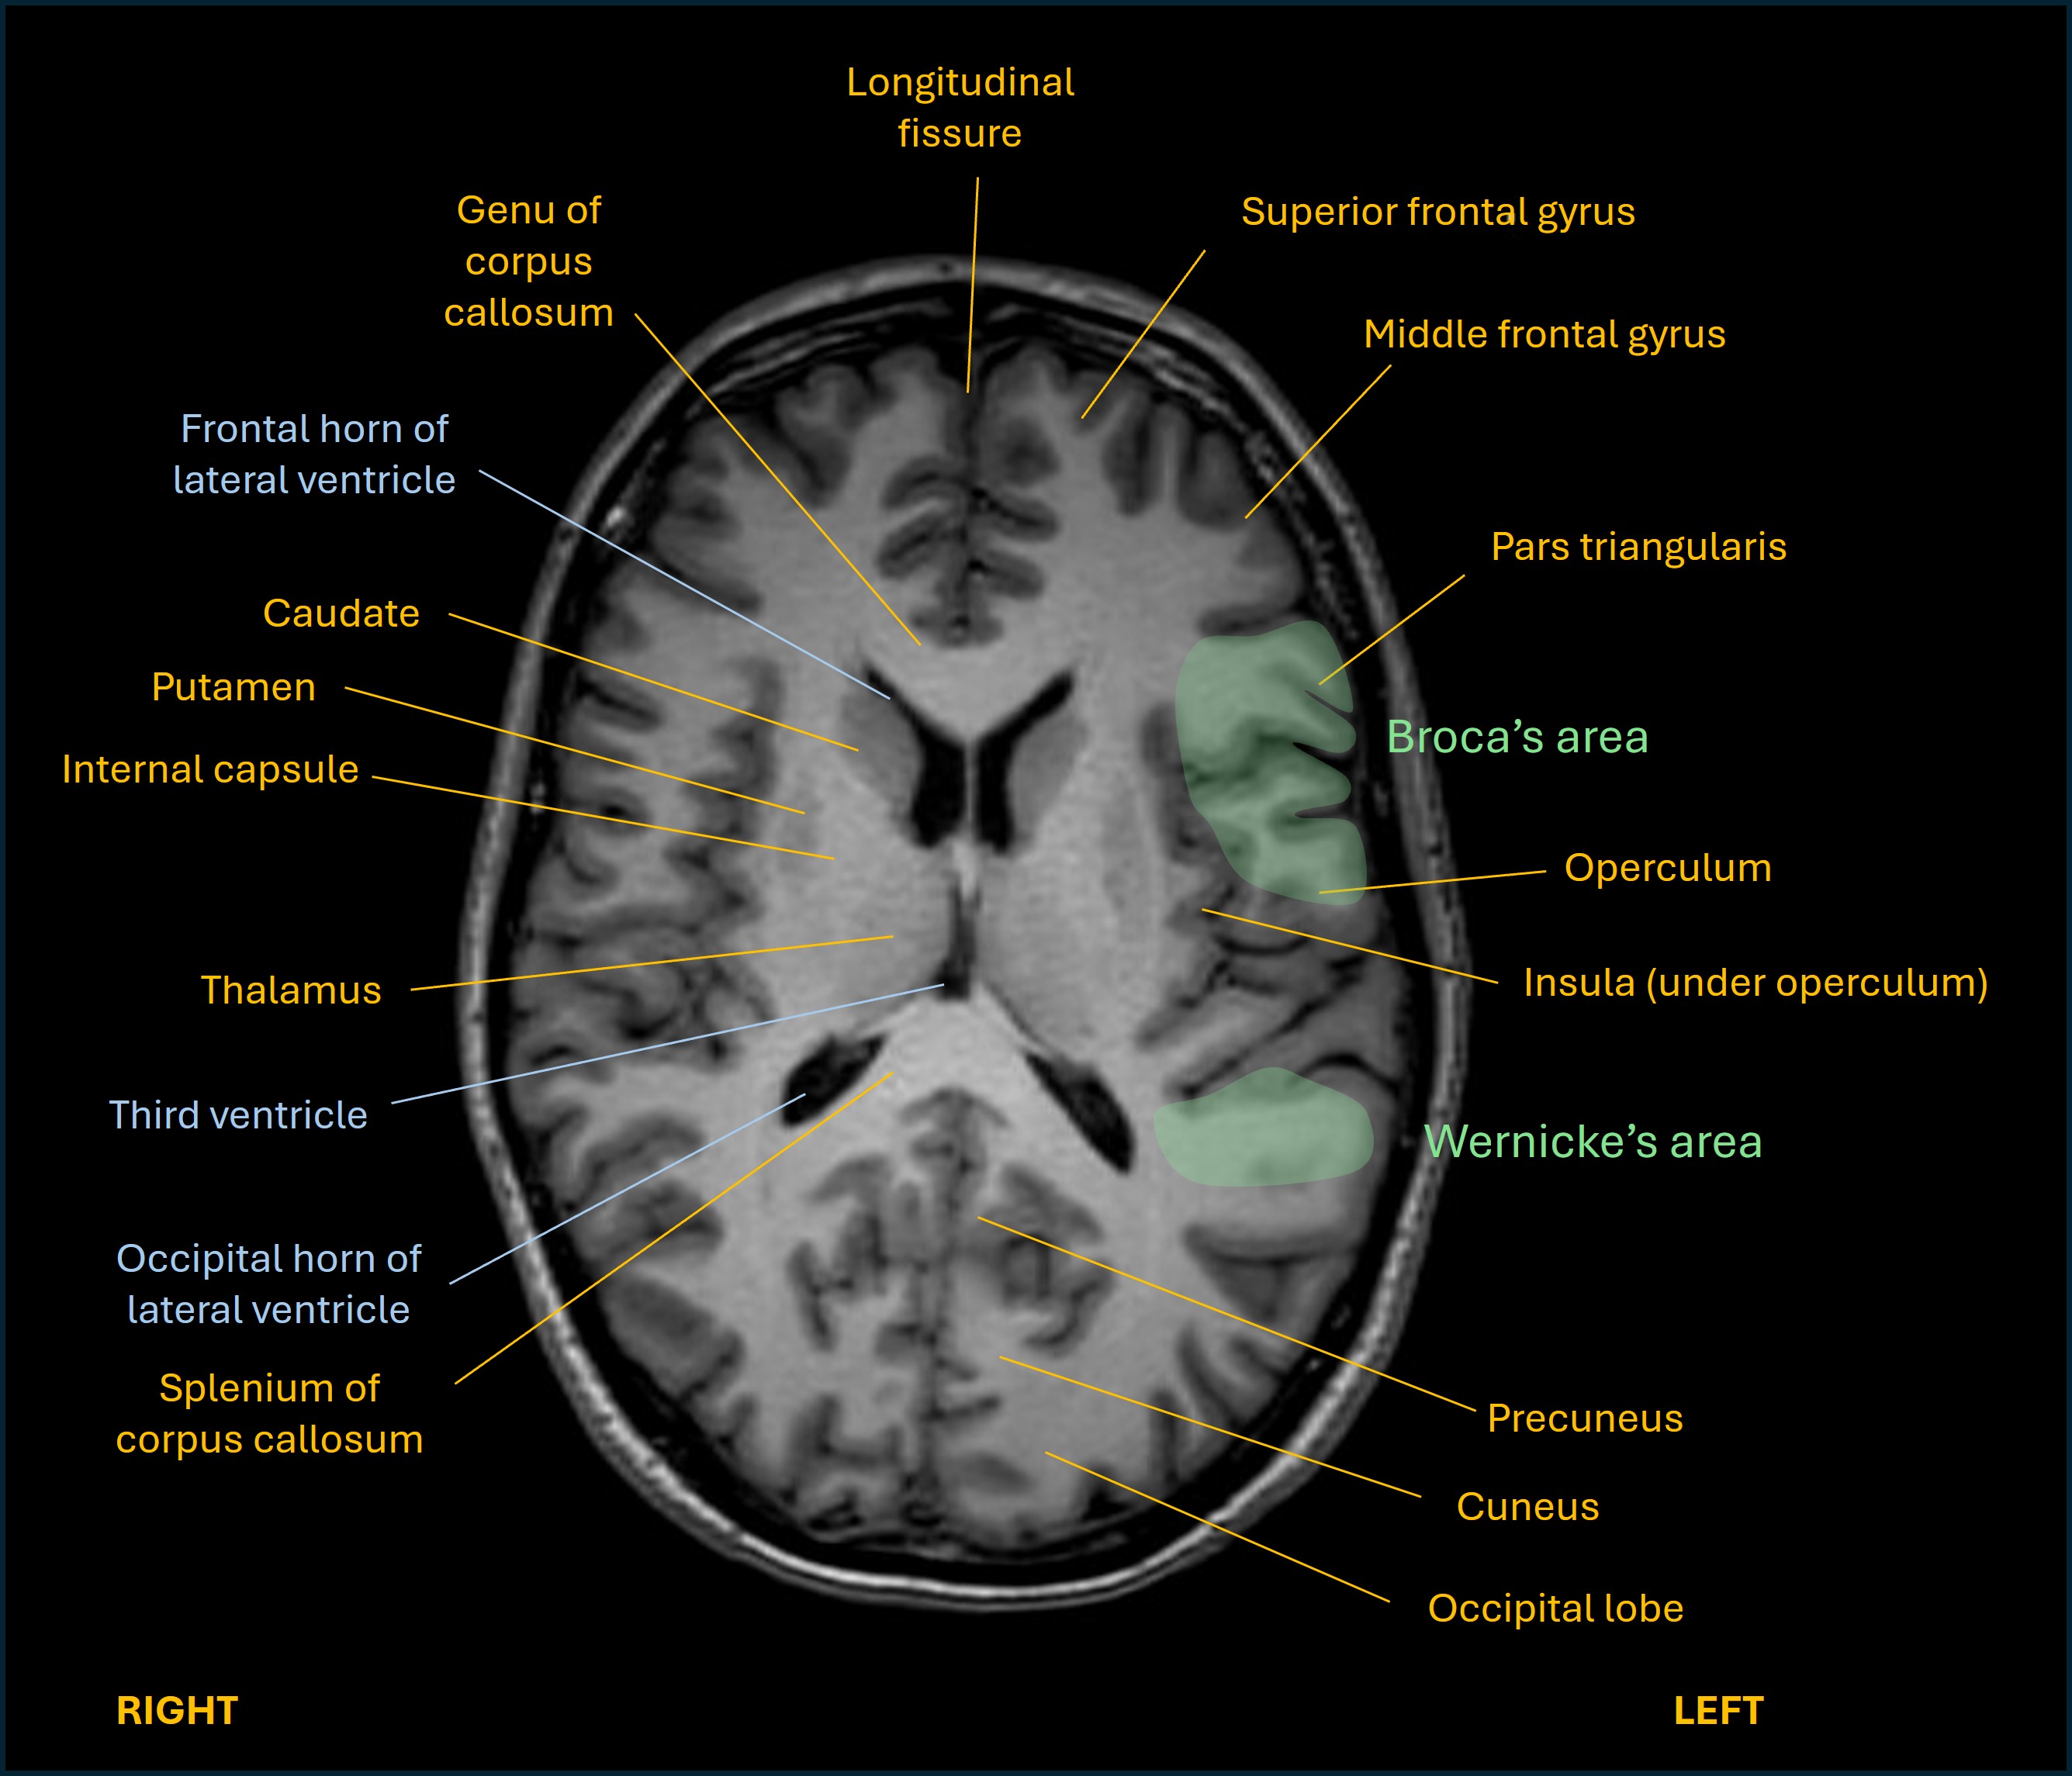

This mixed pattern suggests a lesion somewhere overlapping the left frontal lobe (expressive) and temporal lobe (receptive) language centres, which must involve the subcortical white matter structures connecting these. The fact that the severity is only moderate also fits this - often a lesion centred in the language centre itself produces more profound dysphasia. (Of note, the term aphasia is often used interchangeably with dysphasia - but should really mean a more profound language deficit, or even complete loss of language functions.)

Her dysphasia pattern is different from the two well-known ‘pure’ expressive and receptive forms:

Axial language

Sagittal language